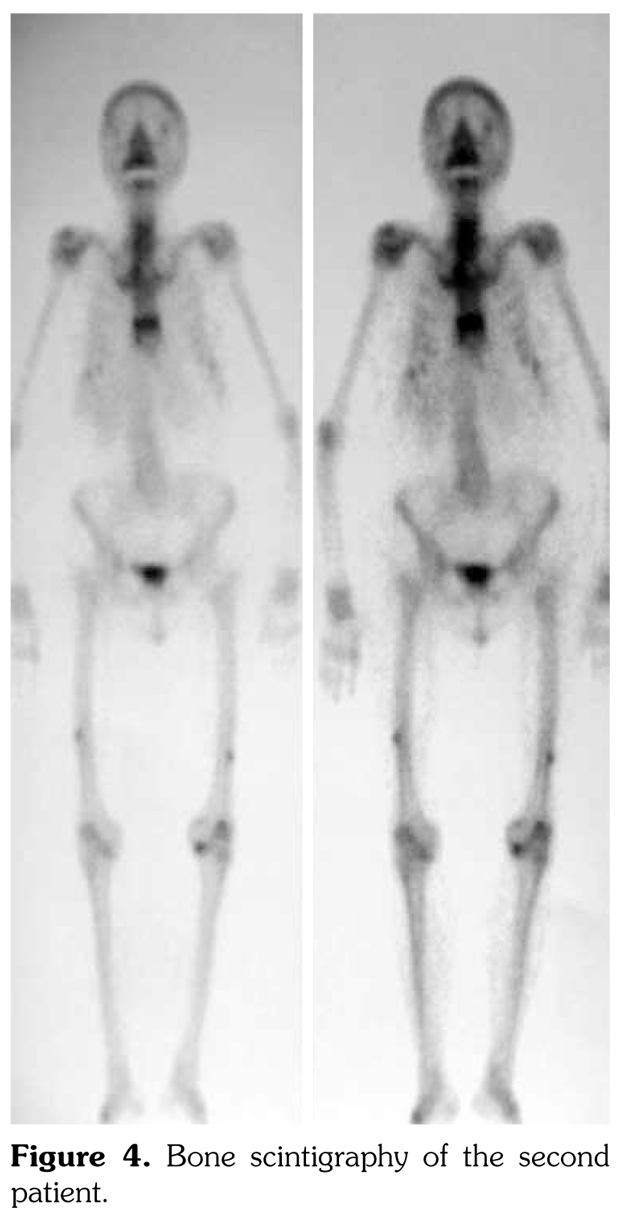

Case 1– A 73-year-old female patient presented with low back, knee, and anterior thigh pain. Pain severity was 8 over 10 point according to visual analog scale. She had difficulty in walking because of pain. She had a history of arthroscopic knee surgery for meniscal pathology in her left knee five years ago. She had chronic low back pain due to L4-5 disc herniation and lumbar spinal stenosis. She had been treated for osteoporosis with alendronate for two years, then with salmon calcitonin for two years and ibandronic acid for a year. Neurological examination was normal. Plain radiographs revealed bilateral lateral cortical thickening in the femur (Figure 1). Magnetic resonance imaging was done to rule out fracture. Bone scintigraphy showed increased uptake in bilateral femoral diaphysis. Routine biochemical tests were normal except increased urinary deoxypyridinoline. Urinary deoxypyridinoline level was 63 nM/mMCre (normal range: 3-7.4 nM/mMCre).

Typical femoral periosteal stress reaction was described as cortical thickening in the lateral side of the subtrochanteric region. In addition, Kwek et al.(5) found bilateral findings of stress reactions or fractures on plain radiographs in 53% of patients on bisphosphonate therapy. In both of our patients, we observed cortical stress reaction bilaterally.

Radiologically, femoral periosteal stress reaction is described as the presence of the dreaded black line which is a transverse black line traversing the cortex that can be complete or incomplete.(6-9) Magnetic resonance imaging findings of femoral periosteal stress reaction include focal cortical thickening, bone edema, focal cortical resorption cavities and dreaded black line. There is an association between radiographic findings and the presence of clinical symptoms.(10) Similarly, our patients had thigh pain and difficulty in walking.